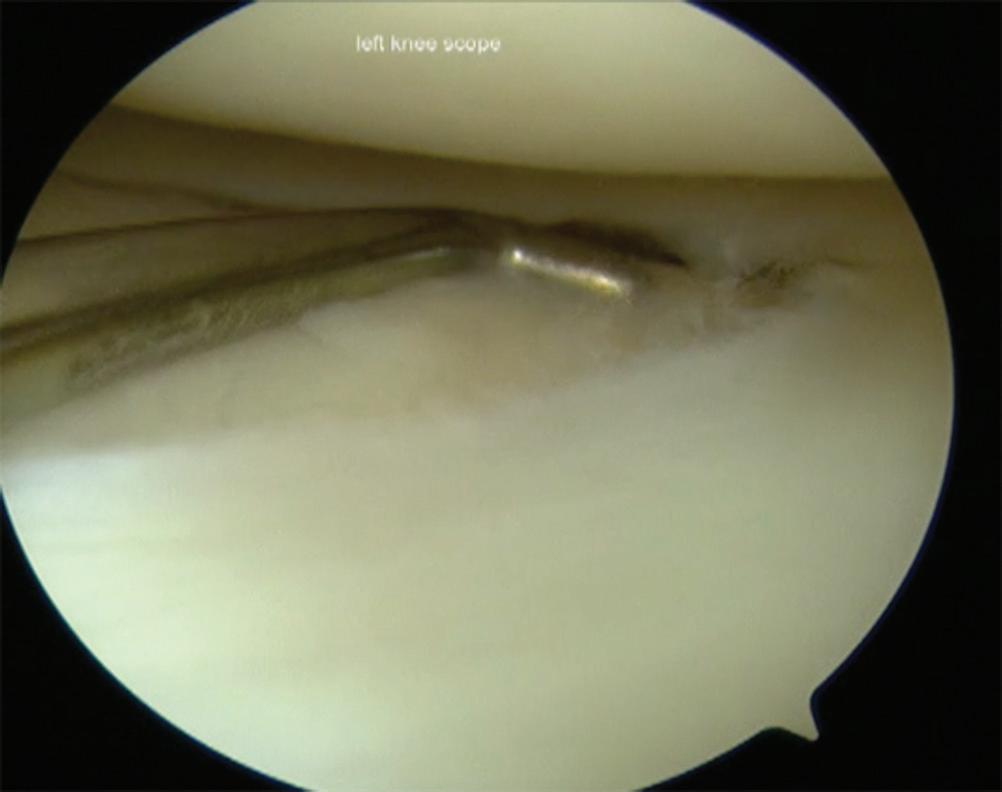

■ Thus, the correct visual orientation of the lateral compartment is maintained. The entire lateral meniscus should be probed and inspected, especially the posterior horn where tears are often missed (Figs. 1-10 and 1-11).

Figure 1-10 Arthroscopic photograph of the left knee shows assessment of the lateral compartment.

Figure 1-11 Arthroscopic photograph of the left knee shows assessment of the lateral meniscus.